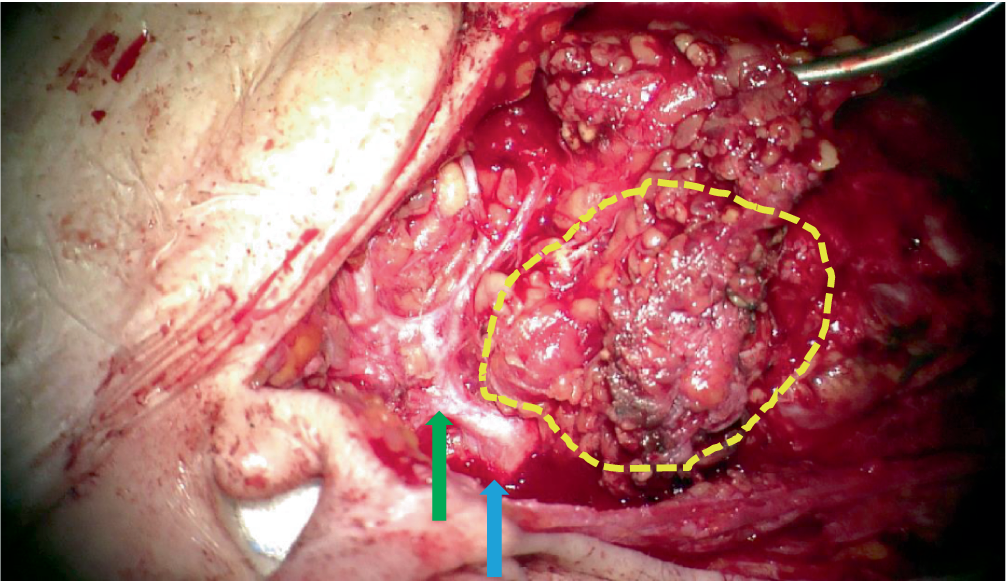

Bei Nachweis eines NUT-Karzinoms in der Stanzbiopsie erfolgte eine totale Parotidektomie rechts mit Resektion des infiltrierten zervikofazialen Hauptasts des N. facialis und Rekonstruktion mit einer HFJ-Anastomose sowie eine modifizierte radikale Neck-Dissection rechts (Abb. 3 und 4).

Abb. 3

Intraparotideal gelegener Tumor: gelb umrandet: palpabler, teilweise sichtbarer Tumor; grüner Pfeil: frontofazialer Hauptast N. facialis; blauer Pfeil: Fazialisstamm